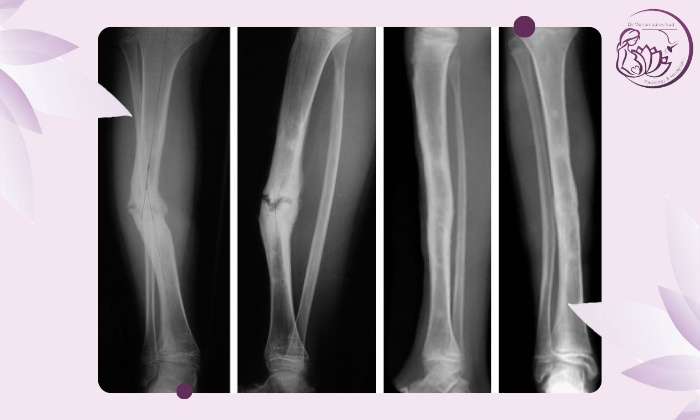

تصویربرداری با رادیوگرافی (X-ray)

رایج‌ترین ابزار تشخیص است. پزشک با مقایسه عکس‌های جدید با تصاویر قبلی موارد زیر را ارزیابی می‌کند:

وجود شکاف بین قطعات استخوان (عدم اتصال)

نبود نشانه‌های تشکیل کال استخوانی (Callus)

حرکتی بودن شکستگی در محل اتصال

در موارد شک‌برانگیز عکس‌ها در دو زاویه گرفته می‌شود تا وضوح بیشتری داشته باشند. چنانچه قصد انجام رادیولوژی در جردن را دارید می‌توانید به مرکز تصویربرداری دکتر محمدنژاد مراجعه کنید.

سی‌تی اسکن (CT-Scan)

در صورتی‌که رادیوگرافی واضح نباشد یا شکستگی پیچیده باشد (مثل شکستگی در نواحی لگن، مچ یا استخوان‌های کوچک):

CT امکان مشاهده سه‌بعدی از محل جوش‌نخوردگی را می‌دهد.

ضخامت و فاصله‌ی بافت استخوانی بین دو قطعه را به‌طور دقیق نشان می‌دهد.

در صورتی که طی ۶ ماه پس از شکستگی هیچ علامتی از ترمیم در عکس‌ها یا علائم بالینی دیده نشود تشخیص این مشکل قطعی است.